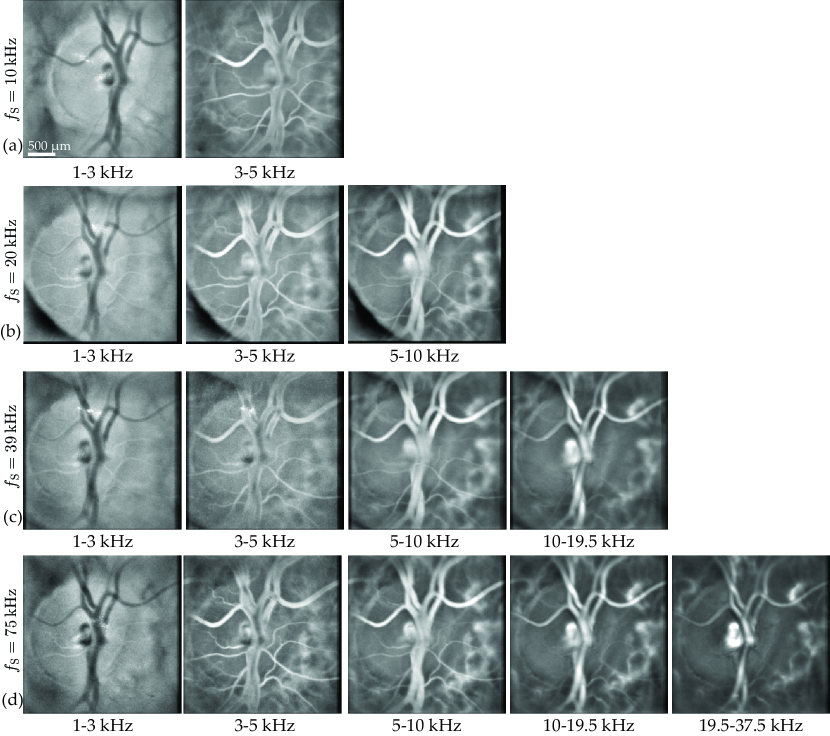

Fig. 8: Multiple laser Doppler holography measurements of a same region are made with different sampling frequencies. For each of these sampling frequencies, PDIs M0+subscript𝑀superscript0M_{0^{+}} are calculated for different frequency bands indicated below the images. (a) fS=10kHzsubscript𝑓S10kHzf_{\rm S}=10\,\rm kHz. (b) fS=20kHzsubscript𝑓S20kHzf_{\rm S}=20\,\rm kHz. (c) fS=39kHzsubscript𝑓S39kHzf_{\rm S}=39\,\rm kHz. (d) fS=75kHzsubscript𝑓S75kHzf_{\rm S}=75\,\rm kHz.

The frequency band [f1,f2]subscript𝑓1subscript𝑓2[f_{\rm 1},\,f_{\rm 2}] used to integrate the DPSD in Eq. (4) is chosen so as to filter off the DC and autocorrelation terms as well as the signals due to global eye movements while keeping the contribution of Doppler shifted light due to pulsatile flow in the vessels. The lower boundary is generally set between 4 and 7kHz7kHz7\,\rm kHz depending on the retinal region being imaged while the upper boundary is set to the camera Nyquist frequency fS/2subscript𝑓S2{f_{\rm S}}/{2}. In Fig. 8, the displayed PDIs are calculated for different frequency bands for each sampling frequency. Each row of the Fig. corresponds to a sampling frequency, fS=10subscript𝑓S10f_{\rm S}=10, 20, 39, and 75kHz75kHz75\,\rm kHz, for the rows (a), (b), (c), and (d), respectively. For each column, M0+subscript𝑀superscript0M_{0^{+}} are calculated for several bandpass interval: [f1,f2]=subscript𝑓1subscript𝑓2absent[f_{\rm 1},\,f_{\rm 2}]= 1-3 kHz, 3-5 kHz, 5-10 kHz, 10-19.5 kHz and 19.5-37.5 kHz from left to right. Except for the acquisition with the highest sampling frequency, some intervals are above the Nyquist frequency of some sampling frequencies and consequently PDIs cannot be calculated for these frequencies. The visualization linked in caption Fig. 8 shows PDIs for a more precise range of frequencies in the case of the acquisition at 75kHz75kHz75\,\rm kHz.

It can be observed in Fig. 8 that for the lowest frequency band 1-3 kHz, the background tissue DPSD is greater than the vessels DPSD, so the vessels appear darker than the tissue on the PDIs. For the frequency band 3-5 kHz, the edges of the large retinal vessel appear brighter than the lumen, as the latter remains dark. That is because the flow is greater at the center of the vessels and the Doppler broadening occurring in these structures is still undersampled. However, for this frequency band, the Doppler broadening caused by the flow in smaller retinal vessels seems adequately sampled as they appear brightly. For frequencies superior to 10kHz10kHz10\,\rm kHz, the DPSD in the lumen seems adequately sampled. Thus integrating lower frequencies allows us to get the signal from smaller retinal vessels, although it also increases the contribution of global axial and lateral movements. It can be noticed that PDIs calculated using a certain frequency band look alike independently from the sampling frequency. For example PDIs calculated with the frequency band 1-3 kHz are virtually the same with the sampling frequencies 10kHz10kHz10\,\rm kHz and 75kHz75kHz75\,\rm kHz. So in the former case, all the signal above 5kHz5kHz5\,\rm kHz (Nyquist frequency for fS=10kHzsubscript𝑓S10kHzf_{\rm S}=10\,\rm kHz) which is aliased has no visible effect on the resulting M0+subscript𝑀superscript0M_{0^{+}} image.

This leads to the conclusion that to make a simple image of the vasculature, the aliased part of the DPSD does not make significant change on PDIs. It is also possible to conclude that the DPSD corresponding to the contributions of pulsatile flow in large vessels lies in frequency bands that are above 510kHz510kHz5-10\,\rm kHz and up to 37.5kHz37.5kHz37.5\,\rm kHz depending on the size of the vessel.